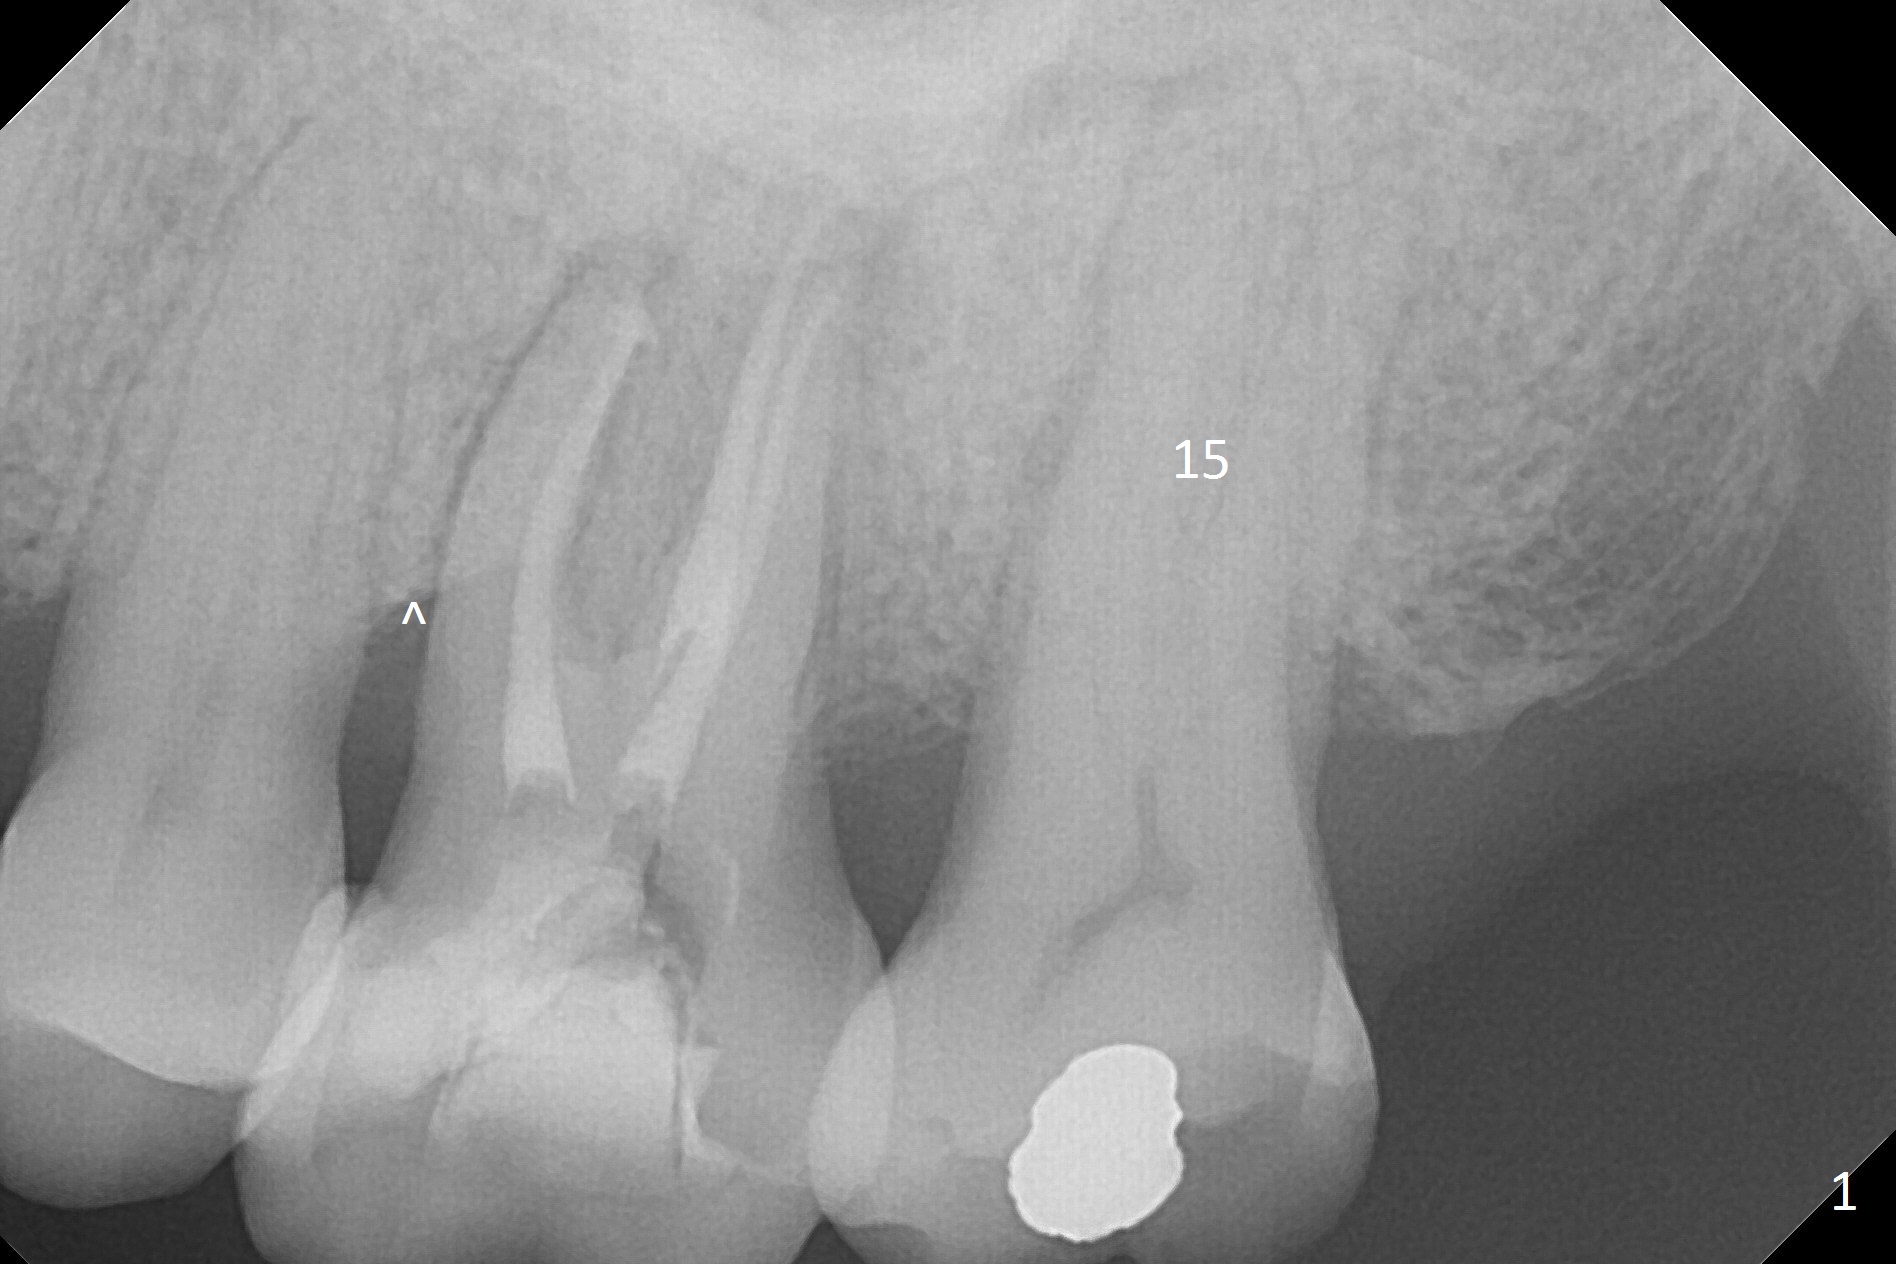

A 70-year-old woman has pain at MB root area post RCT at #14 (Fig.1,2). The tooth seems to have endo-perio disease (bone loss with gingival recession at MB) and be non-salvageable. After extraction and Metronidazole treatment, start osteotomy with 1.6 mm drill 1-2 mm shy of the sinus floor, followed by PA. Use Lindamann bur for ostetoomy position and trajectory adjustment. Use Marking Bur if necessary before Magic Drill 4.3 mm if the septum is wide. The depth of the osteotomy is 1-2 mm coronal to the sinus floor. Do not use the final drill, i.e., saving the osteotomy plug in place. Next 4.5x11 mm dummy implant is placed to push the plug upward for lifting. Place an implant as large as possible, but not violating the buccal gap (Fig.3).

The patient must be a bruxer, since the roots of the tooth #15 is long (Fig.1). The immediate provisional should have occlusal clearance.